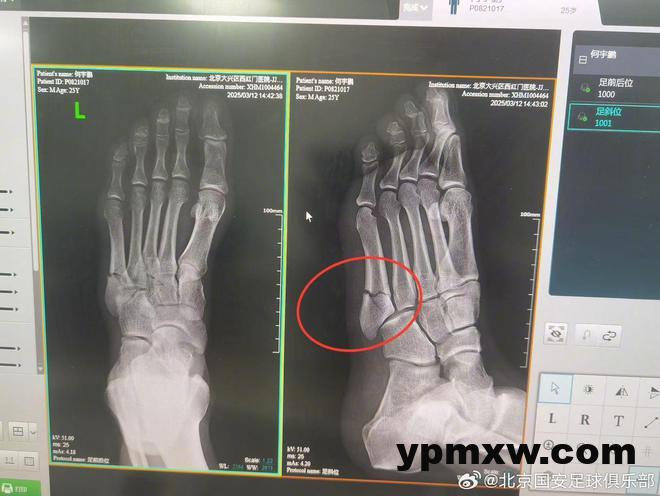

2025年3月12日,队内有球对抗训练时,何宇鹏不慎扭伤左足,当即感到左足外侧剧烈疼痛。队医立即紧急处理,判断为左足第五跖骨骨折可能,并立即冷敷加压特殊处理后,去医院进行影像检查。

经左足X光片提示,诊断结果为:左足第五跖骨基底部粉碎性骨折。